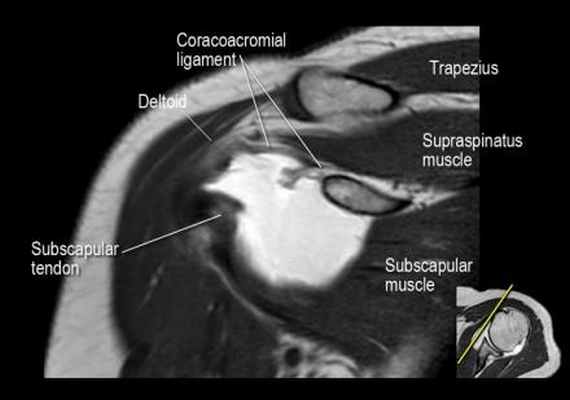

Нормальная корональная анатомия плечевого сустава и контрольный список

- обратите внимание на клювоакромиальную связку (coracoacromial ligament).

- -

- обратите внимание на надлопаточный нерв и сосуды (suprascapular nerve and vessels)